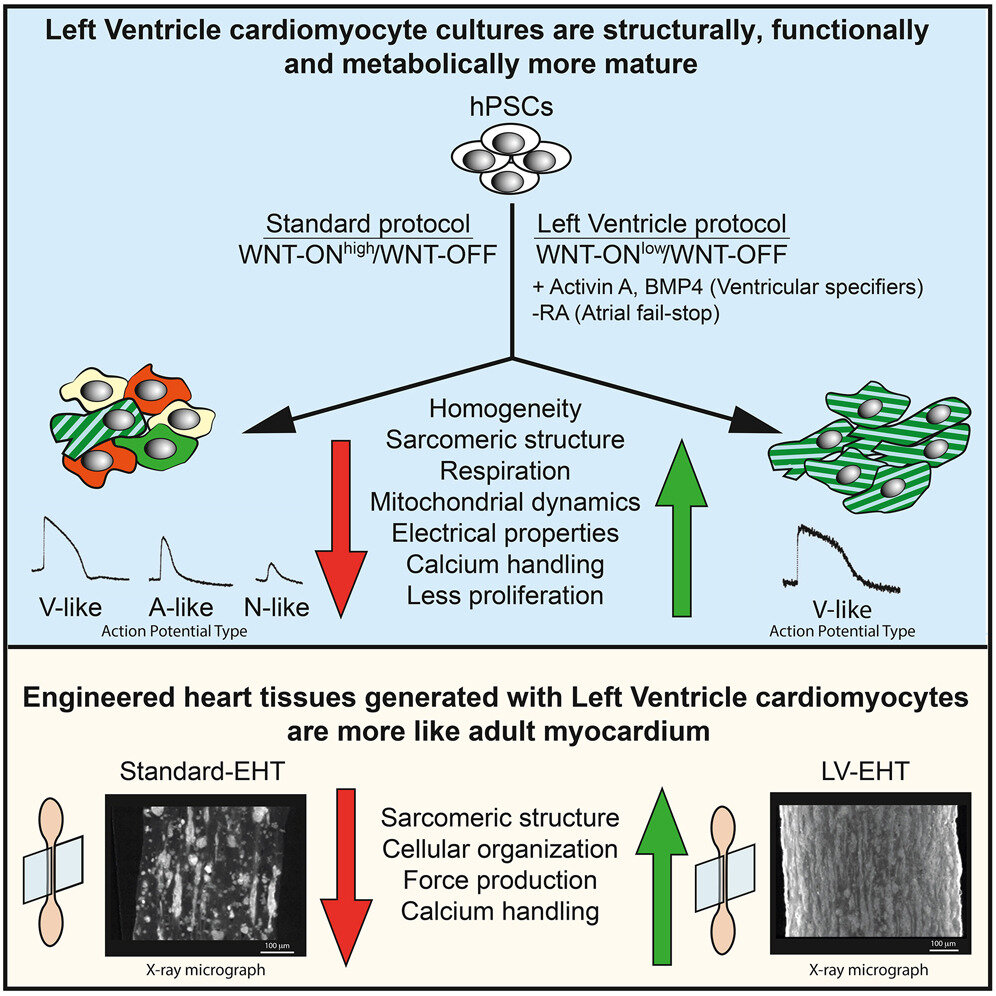

A Heartbeat In A Dish Growing Specialized Heart Cells